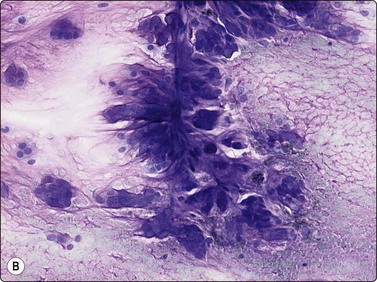

Proliferative myositis and fasciitis are less frequent pseudosarcomatous processes but are important with regard to the rapid growth (common to all these lesions) and their occurrence in children. Their cytomorphology is similar to that of nodular fasciitis although the myxoid matrix is less prominent and the ganglion cell-like cells are often numerous with very prominent nucleoli (Fig. 15.3). In proliferative myositis regenerating multinucleated muscle fibers are commonly present (Fig. 15.4). An important clinical sign is that these lesions, especially nodular fasciitis, can disappear spontaneously or diminish substantially in size within 3–4 weeks after needling.15,16 Another lesion which cytologically demonstrates prominent reactive cellular changes is pseudomalignant myositis ossificans (PMO). PMO is a rapidly growing lesion (intramuscular or subcutaneous), smears showing a mixture of proliferating fibroblasts/myofibroblasts, osteoblasts with prominent reactive changes and multinucleated giant cells of osteoclastic type (Fig. 15.5). In PMO an ossification in a zonal pattern is a typical find within 3–4 weeks and, according to our experience, spontaneous resolution is common. The cytomorphology in our series of five cases17 is similar to that described by Dodd et al.13

image

Fig. 15.3 Proliferative fasciitis

Ganglion cell-like cells are often numerous with very prominent nucleoli (H&E, HP).

Fig. 15.4 Proliferative myositis

Regenerating muscle fibers are commonly present (MGG, HP).